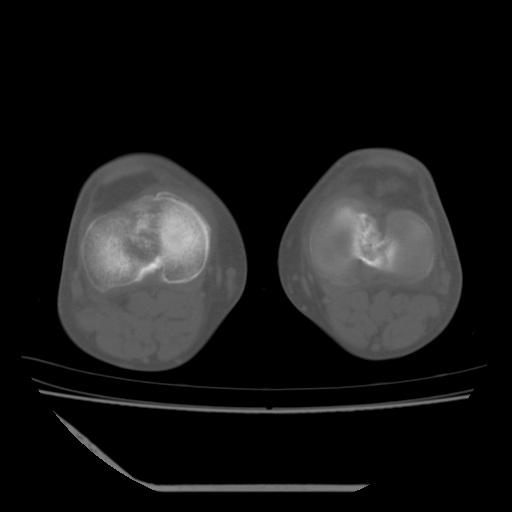

标题: CT13225:老年男性,左膝关节疼痛数月;请各位老师讨论。 [打印本页]

标题: CT13225:老年男性,左膝关节疼痛数月;请各位老师讨论。

骨质增生,骨性关节面硬化,关节积液,考虑退行性骨关节病

关节腔内少量积液,关节面退变。

双膝退变

骨质增生,骨性关节面硬化,关节间隙失常,关节积液,考虑退行性骨关节病.

这个病例诊断:退行性骨关节炎